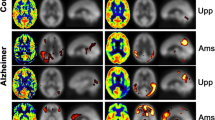

Arterial Spin Labeling (ASL) is an emerging magnetic resonance imaging technique attracting increasing attention in dementia diagnosis only beginning from recent years. ASL is capable to provide direct and quantitative measurement of cerebral blood flow (CBF) of scanned patients, so that brain atrophy of demented patients could be revealed by measured low CBF within certain brain regions through ASL. However, partial volume effects (PVE) mainly caused by signal cross-contamination due to pixel heterogeneity and limited spatial resolution of ASL, often prevents CBF from being precisely measured. Inaccurate CBF is prone to mislead and even deteriorate dementia disease diagnosis results, thereafter. In this paper, a novel dementia disease diagnosis strategy based on ASL is proposed for the first time. The diagnosis strategy is composed of two steps: 1) to conduct pixel-wise PVE correction on original ASL images and 2) to predict dementia disease severities based on corrected ASL images via ranking. Extensive experiments and comprehensive statistical analysis are carried out to demonstrate the superiority of the new strategy with comparison to several existing ones. Promising results are reported from the statistical point of view.